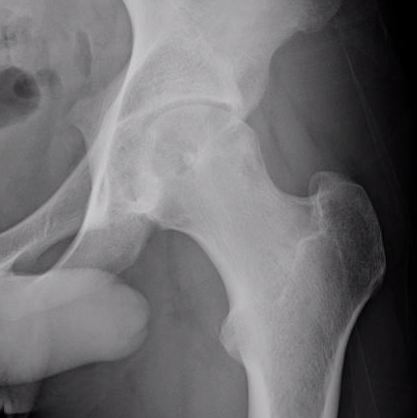

Femoral head osteoblastoma

- 14 cases

- open dislocation and modified trapdoor approach

- no local recurrence

- one case AVN requiring joint replacement